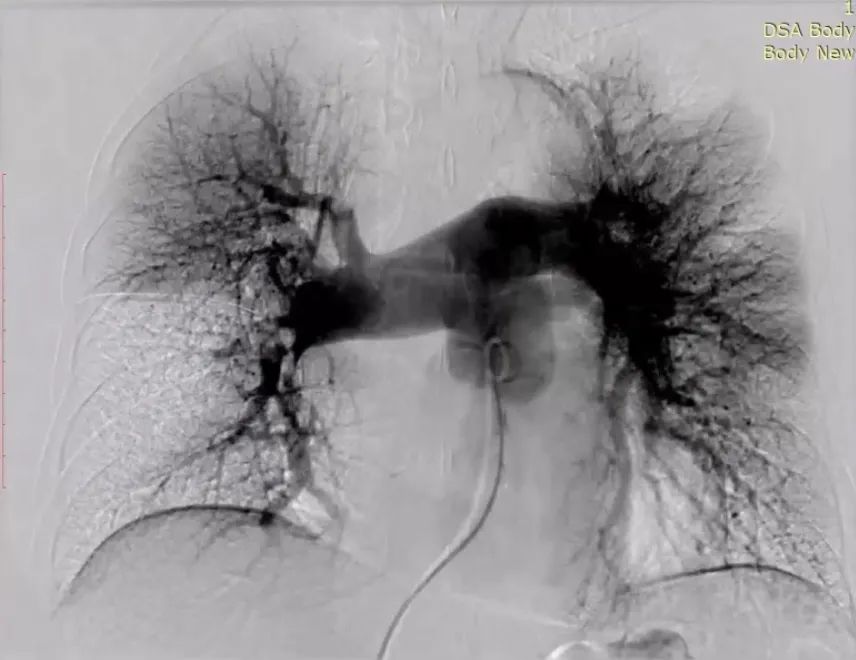

术前

患者双肺血栓负荷大,且氧饱和度较低,为降低肺栓塞的高危恶化风险,仔细评估手术风险和指征,拟行经导管肺动脉取栓术。术中建立右心房-右心室-肺动脉通路,抽吸导管沿导丝送至肺动脉,管口贴近血栓处停止,撤出内芯,将取支架沿导丝通过抽吸导管向前推送,再回撤输送鞘,支架自动打开,连接负压抽吸器,回撤取栓支架的同时旋转开关释放负压,血栓在支架及负压的作用下进入抽吸导管中并带出体外。